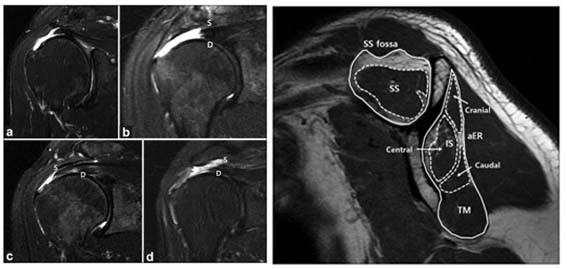

| | ¨Ï ¿Â¾ç½Å¹® | õ¾È¡¤¾Æ»êÃæ¹«º´¿ø Á¤Çü¿Ü°ú À¯À缺 ¹Ú»ç<»çÁø>°¡ Ã¥ÀÓÀúÀڷμ ¾î±ú ÈûÁÙ ¼Õ»óÀÇ ÇØºÎÇÐÀû ±¸Á¶¿¡ ´ëÇÑ ¿¬±¸À¸·Î SCI±Þ ±¹Á¦ ÇмúÁö¿¡ ³í¹®À» ¹ßÇ¥ÇÞ´Ù°í ¹àÇû´Ù.

À¯À缺 ¹Ú»çÀÇ Á¤Çü¿Ü°ú ¼ö¼ú °ü·Ã SCI(E)±Þ ±¹Á¦ÇмúÁöÀÎ ¡®Indian Journal of Orthopaedics¡¯¿¡ °ÔÀçµÈ ¡®Relation of Superfcial and Deep Layers of Delaminated Rotator Cuff Tear to Supraspinatus and Infraspinatus Insertions¡¯ ³í¹®Àº ¾î±úÀÇ È¸Àü±Ù°³ ÆÄ¿ ¾ç»ó¿¡ µû¸¥ ȸÀü±Ù°³ ±ÙÀ° º¯È ¾ç»ó¿¡ ´ëÇØ ºÐ¼®ÇÏ¿© ȸÀü±Ù°³ ÆÄ¿ÀÇ ÇØºÎÇÐÀû ±¸Á¶¿¡ ´ëÇÑ ¿¬±¸ÀÌ´Ù.

| | ¡è¡è ¡ãȸÀü±Ù°³ ±ÙÀ°ÀÇ º¯È <»çÁøÁ¦°ø=¾Æ»êÃæ¹«º´¿ø> | ¨Ï ¿Â¾ç½Å¹® | | ´ëÇѹα¹ Çڵ庼 ±¹°¡´ëÇ¥ ÆÀ´ÚÅͷΠȰµ¿ ÁßÀÎ À¯À缺 ¹Ú»ç´Â ´Ü±¹´ëÇб³ Á¤Çü¿Ü°ú ±³¼ö ÀçÁ÷ ÁßÀÌ´ø 2017³âºÎÅÍ ¡®¸¶¸£ÄûÁî ÈÄÁî ÈÄ ÀÎ ´õ ¿ùµå(Marquis Who¡¯s Who in the World)¡¯¿¡ µîÀçµÇ¾úÀ¸¸ç, ¾î±ú ¹× ÆÈ²ÞÄ¡ °üÀý ¼ö¼ú °á°ú¿¡ ´ëÇÑ ÀÓ»ó ³í¹®À» SCI±Þ Àú³Î 22ÆíÀ» Æ÷ÇÔÇÏ¿© ÃÑ 80¿© ÆíÀÇ ³í¹®À» °³Á¦Çß´Ù.